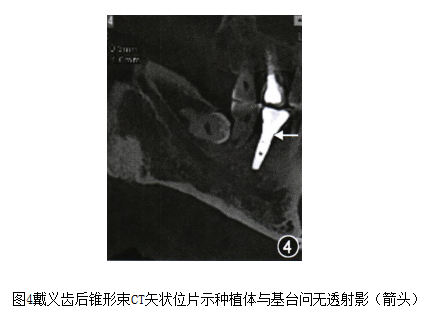

处理:去除愈合基台,试戴后拍摄锥形束CT片(如图4)。

图4.png

调牙合、嘱保持口腔卫生,1个月后复诊。